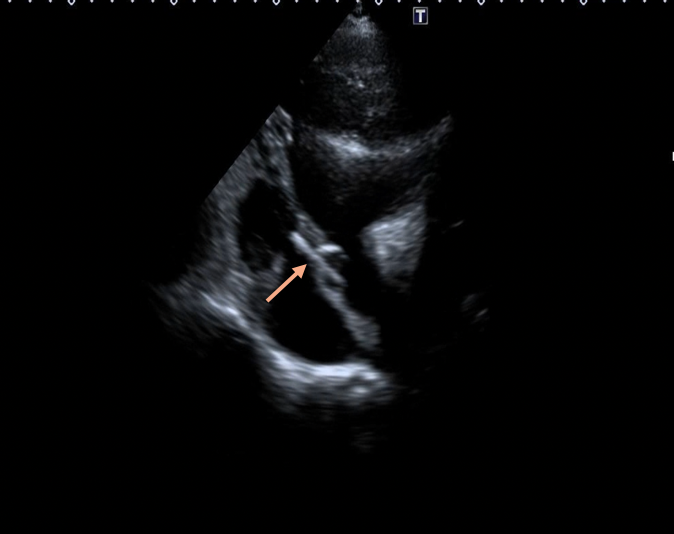

Gentle traction was exerted on the delivery cable to confirm seating of the left disc on the aortic side without slippage into the ruptured SVA. The rest of the occluder was deployed on the right side across the lesion (Figure 5A-B, Videos 5A-B).

Figure 5. (A) Device deployed (purple arrow). (B) Transthoracic echocardiography.

(Figure 5B)